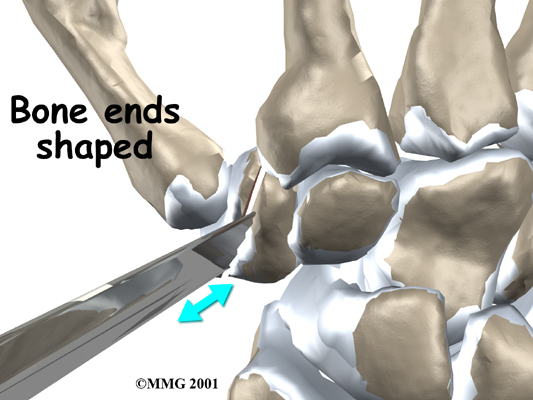

In this procedure, an incision is made across the base of the thumb. The soft tissues are spread apart with a retractor. Special care is taken not to damage the nearby nerves going to the thumb. The joint capsule is opened, exposing the CMC joint. The ends of the bones that form the CMC joint surfaces are taken off, forming flat surfaces.

A burr (a small cutting tool) is used to make a canal into the bones that form the thumb joint. The surgeon sizes the stem of the prosthesis to ensure a snug fit into the canal and inserts it. When the new joint is in place, the surgeon wraps the joint with a strip of nearby tendon. This gives the new implant some added protection and stability.

A new method for replacing the thumb joint is to use a spherical implant that looks much like a marble. The surgeon makes a small, one-inch incision at the base of the thumb joint. The ends of the bones that form the CMC joint surfaces are removed, forming flat surfaces.

A burr is used to make a small notch, or canal, in the ends of the two bones. The surgeon shapes the notch so the ball-shaped implant will fit snugly in the joint. The implant is placed between the ends of the shaped bones.

View animation of joint surface removal